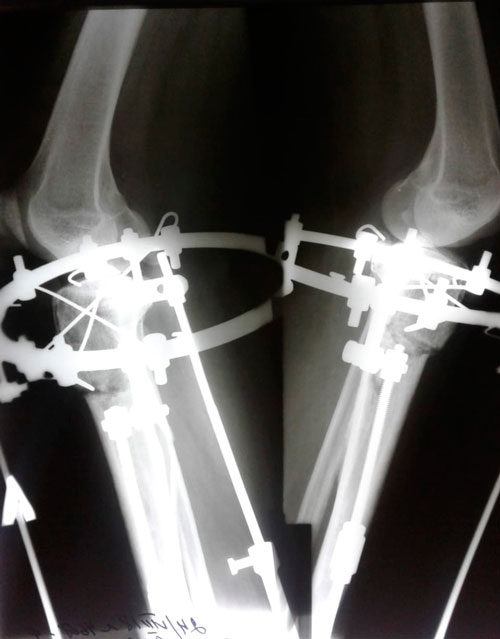

Дата операции 22.06.2018г.

Дата снятия - 02.11.2018г.

Срок сращения - 98 дней.